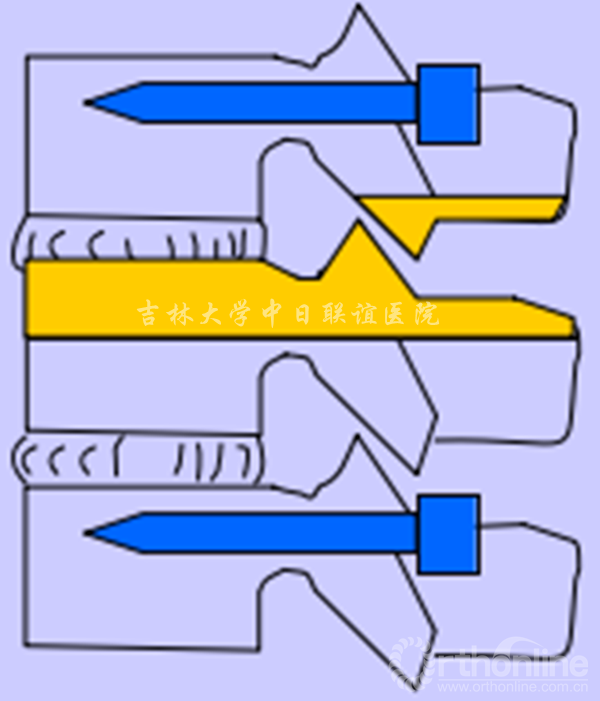

2.脊柱短缩截骨术(Spine-shortening Osteotomy)

A1.B1:T12/L2植入椎弓根螺钉后,切除T12下1/2及L1上1/3椎板及T12/L1关节突;

A2.B2:磨钻磨除L1上3/4椎弓根,并经磨除的椎弓根磨除L1椎体上部分,然后切除T12/L1间盘及后纵韧带;

A3.B3:截完后的脊柱形态。截骨线应平行于L1下终板和T12上终板;

A4.B4:截完后的空间通过T12/L2钉棒系统逐渐加压闭合。

2.2 脊柱短缩截骨的部位(脊柱短缩截骨常行L1截骨)

2.3 脊柱短缩截骨的长度

胸腰段20-25mm脊柱短缩可以充分地减小栓系脊髓的张力。

目前认为脊柱短缩截骨约20mm较为安全,同时可有效减小栓系脊髓张力。